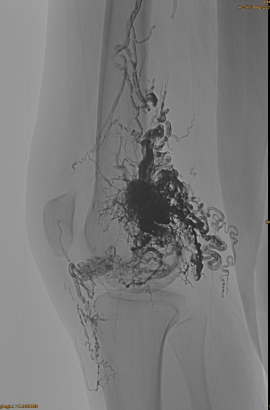

환자의 기본 정보 : 여성, 36 년; AVM 골반, 엉덩이, 무릎, 왼쪽 OSG, 다중 사전 - 색전증.

사용되는 제품 : 3PCS Lava-34,14pcs Lava-18.

초기 DSA :

최종 결과 :

정맥 유출은 거의 없습니다.

늦은 단계, 또 다른 EMBO가 필요하지만 훨씬 좋습니다.